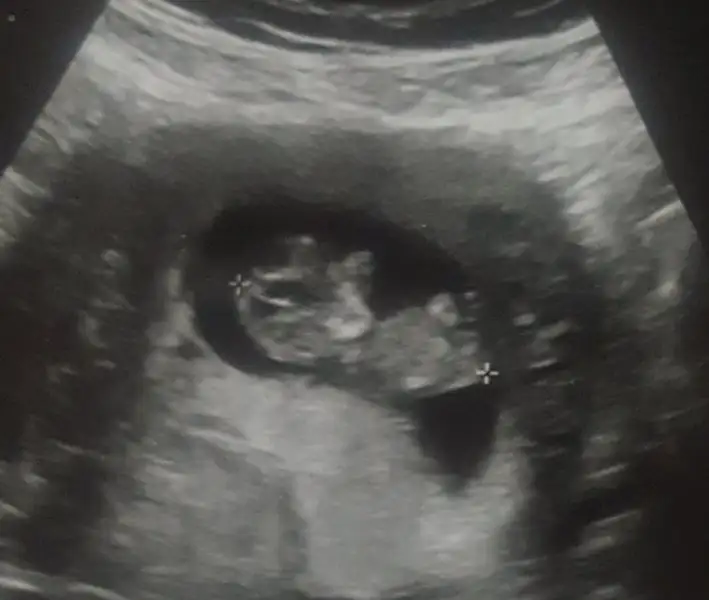

Kızlar nubtan cinsiyet tahmini varmış anlayaniniz var mıı 20171111_194241.webp

Ayy masallah haftalarimiz ayni ben 29una gorecegim insallah minigimi en son gordugumde 7 haftalikti simdi boyle buyumus bebek goruntusu olmasi beni cok duygulandirdi insallah benim minigimde boyledir masallah bu minige:KK200:

Evet canım ya baya baya bebeğe benziyordu bu sefer,gözleri burnu elleri ayaklari.. inşallah sen de böyle hatta daha büyük görürsün. 25inde bı daha gidecem :halay:

göremedim dedi canım, kız senin gözüne gözüne sokmuş dediğin göbek kordonu :KK70::KK70::KK70:

Yok ben kordonu kastetmedim. Bacak arası kısmı net görülüyo gibi geldi bana. Biz bakınca anlamıyoruz tabi ama dr anlamıştır diye düşündüm:KK57: